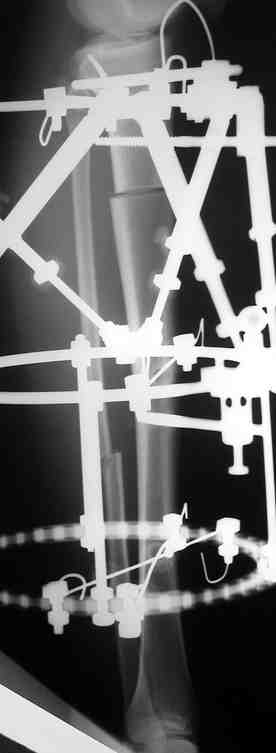

Выше приведены рентгенограммы 13-летнего подростка, страдающего от огнестрельного многооскольчатого перелома дистальной трети бедра. AO наружный фиксатор наложенный в день травмы не дал приемлемой редукции. Через три недели после перелома аппарат Илизарова был наложен без попытки одномоментной репозиции на операционном столе. There are X-Rays of a thirteen year old boy with a comminuted distal femur fracture secondary to a gunshot wound, initially treated with an AO external fixator. The alignment was unacceptable and an Ilizarov external fixator was applied three weeks after the injury. No attempt of definitive reduction was made during the surgery.

Гексаподная приставки наложена на 10 дней и приемлемая редукция была получена. The Hexapod set was applied for ten days and acceptable reduction was received.

По окончанию редукции Гексаподный сет был снят и дальнейшее ведение больного проходило в стандартном режиме аппарата Илизарова. Хороший анатомо-функциональный результат был получен. When reduction was finished, the Hexapod set was removed and further management has been continued by standard Ilizarov regime. Good anatomic and functional results were achieved.